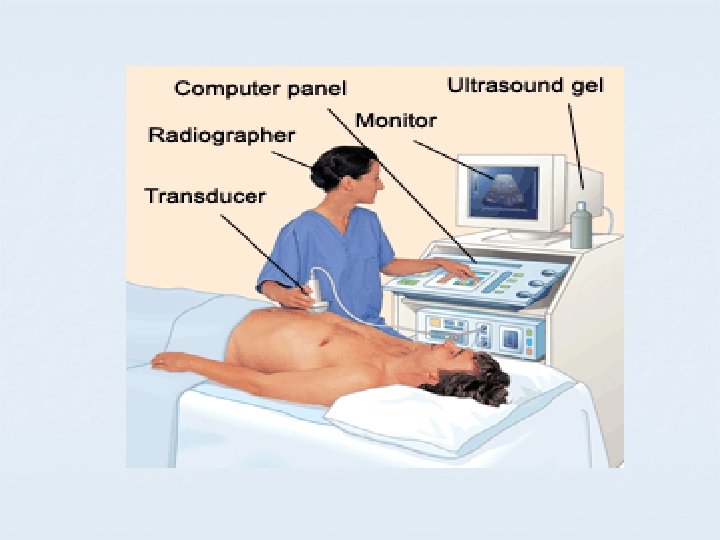

ULTRASOUND IMAGING The creation of an image from sound is done in three steps - producing a sound wave, receiving echoes, and interpreting those echoes. The probe plays the major role in constructing image.

ULTRASOUND APPARATUS

The Ultrasound Equipment Components: 1. The probe. 2. The control panel. 3. The freeze frame. 4. Measuring facilities. 5. A means of storing images.